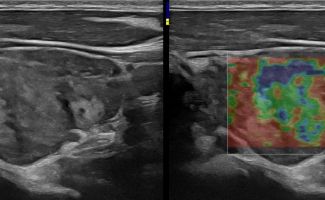

Με την τριπλή μελέτη του Θυρεοειδούς Αδένα, που περιλαμβάνει το B-Μode, το Έγχρωμο Υπερηχογράφημα και την Ελαστογραφία, γίνεται μια ολοκληρωμένη χαρτογράφηση του θυρεοειδούς αδένα. Το περίγραμμα, η αγγείωση και η ελαστικότητα του αδένα, καθώς και η υφή μίας πιθανής βλάβης αξιολογούνται με ακρίβεια και αξιοπιστία.